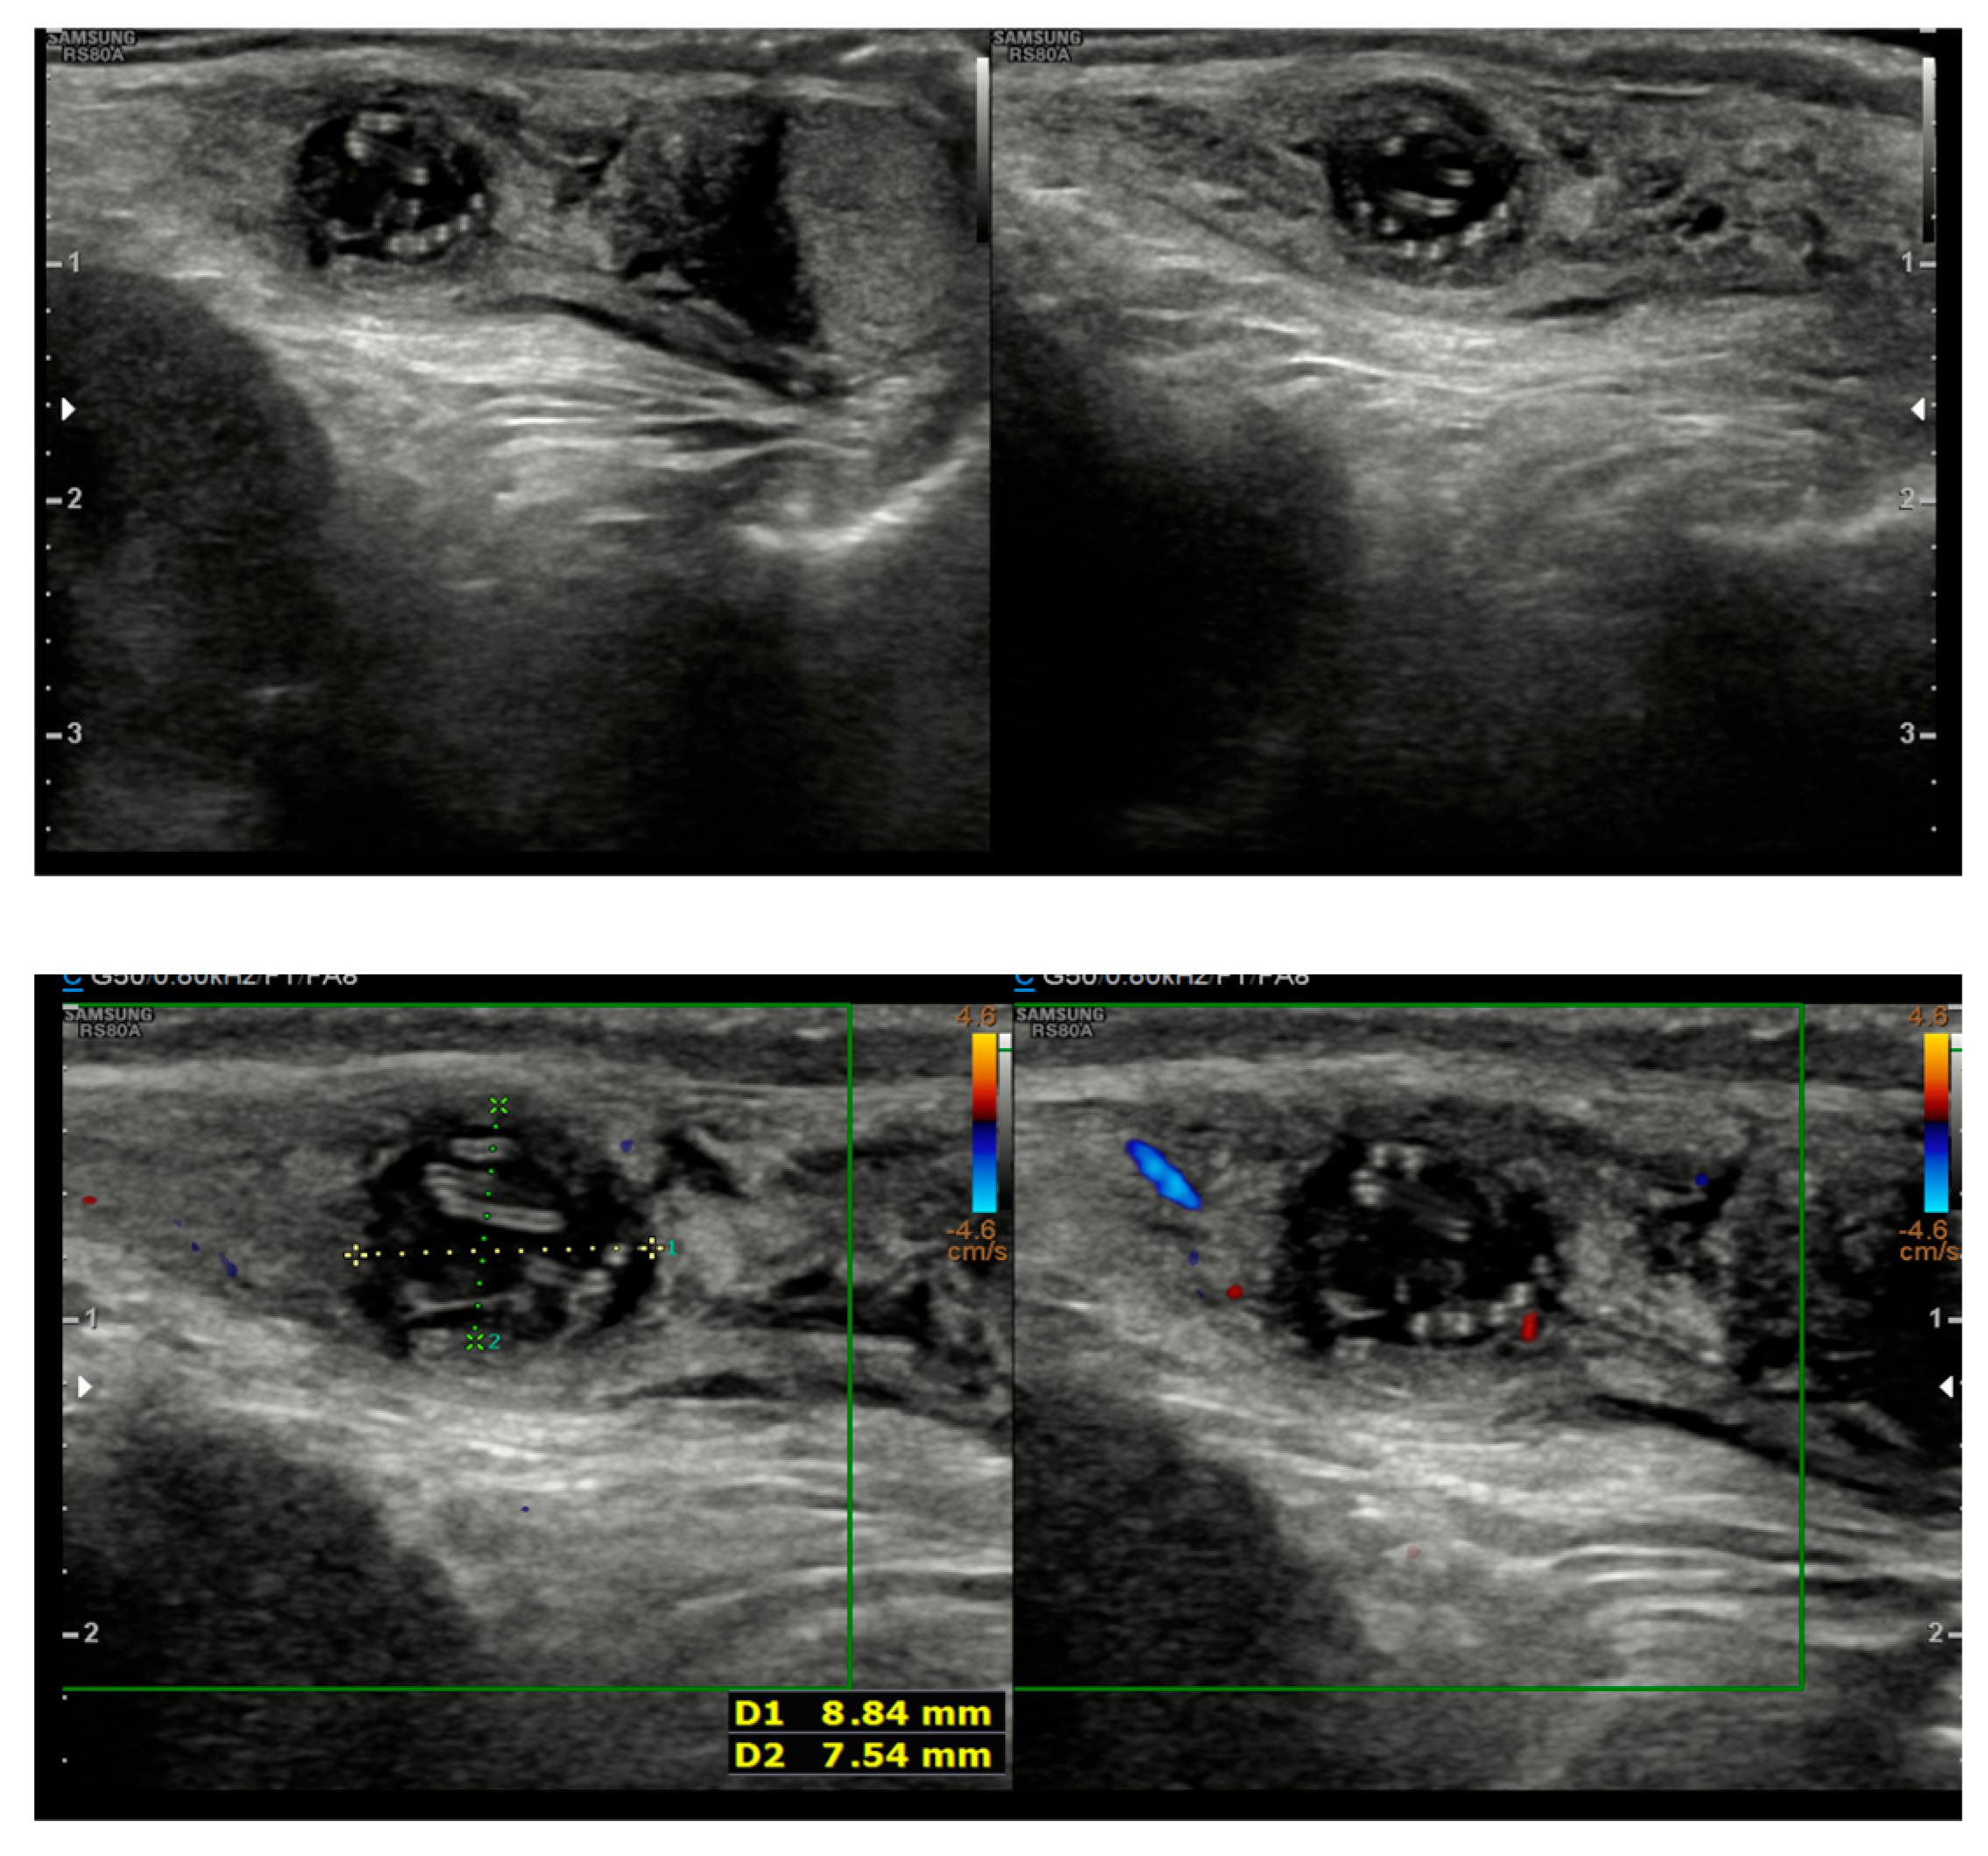

A 5-year-old boy, born in Catania, Sicily, Italy, to a Sri Lankan migrant family, was evaluated for left testicular pain and swelling. He had no prior hospitalizations or significant medical history. He was fully vaccinated. The symptoms were initially attributed to orchiepididymitis, as the left testis was edematous, painful, and hyperemic. The patient was treated with oral amoxicillin/clavulanate and nonsteroidal anti-inflammatory drugs (NSAIDs) for 10 days. There was mild improvement in swelling, but testicular pain persisted. Laboratory tests, including blood counts and inflammatory markers, showed only mild thrombocytosis (415,000/mmc). An ultrasound performed at the Pediatric Emergency Department of Garibaldi Nesima Hospital in Catania showed thickening of the left spermatic cord with increased blood flow on Doppler, while the testes appeared normal in morphology, and no hydrocele was present (Figure 1). Two weeks later, at a follow-up visit, the boy’s symptoms had worsened. A firm, elastic, mobile mass was palpated in the left inguinal/scrotal area, distinct from the right testis. The testis ultrasound at that time revealed a well-defined, round hypoechoic mass (measuring 8.5 mm) with linear hyperechoic structures within it (Figure 2).

Figure 2.

Follow-up ultrasound demonstrating a hypoechoic nodule containing linear hyperechogenic lines.

The differential diagnosis at this stage included torsion or detachment of the appendix testis (hydatid of Morgagni) versus a granulomatous infection or neoplasm. Given the uncertainty and persistence of the mass, an exploratory surgical intervention was performed. The pediatric surgeons excised an encapsulated, tough mass from the left spermatic cord (Figure 3). The mass was not adherent to the testis or epididymis. Histopathological analysis of the nodule revealed a pseudocyst with chronic granulomatous inflammation, containing fragments of helminth, surrounded by fibrinous and purulent exudate (Figure 4).

The inflammatory reaction seen in this patient is a characteristic feature of these infections and is often linked to the host’s immune response against a dying or degenerating worm, which can lead to the release of worm antigens or symbiotic Wolbachia bacteria [16]. In our case, we did not identify Wolbachia antigens. Imaging played a key role in guiding the diagnosis. While initial ultrasound findings were non-specific, the follow-up imaging revealed a nodule containing linear hyperechogenic structures. Although worm motility was not observed, this “worm-in-a-bag” sign is highly suggestive of an encysted helminth [17]. Awareness of these sonographic features is critical for clinicians to distinguish these lesions from tumors, as misdiagnosis has previously led to unnecessary orchiectomies [6,18].